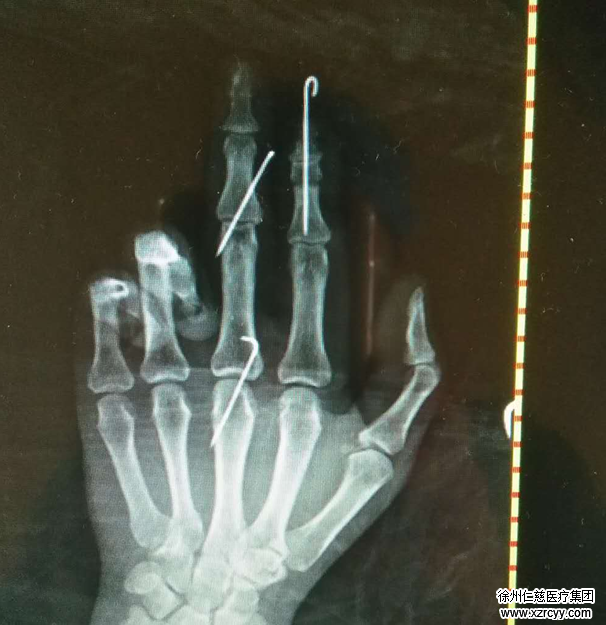

熊医生为患者申请了急诊绿色通道,患者被紧急送入手术室行再植手术。由于患者右示中指离断指体血管抽出并碾挫伤严重,而且缺损至指总动脉,术中手术小组予前臂切取皮下“Y”型静脉,移植桥接、重建指总动脉及示中指指动脉,恢复中指离断指体及示指近中节指体血供;示指远节脱套离断指体血管缺损,再次于前臂切取皮下静脉桥接重建远节脱套离断指体血供。同时保存了中指的指间关节,可以使患者右手的功能得到最大程度的恢复。手术历经5小时,右手示中指离断指体再植成功。

术中摄片情况:保存了中指的指间关节,可使手指功能得到最大程度恢复。